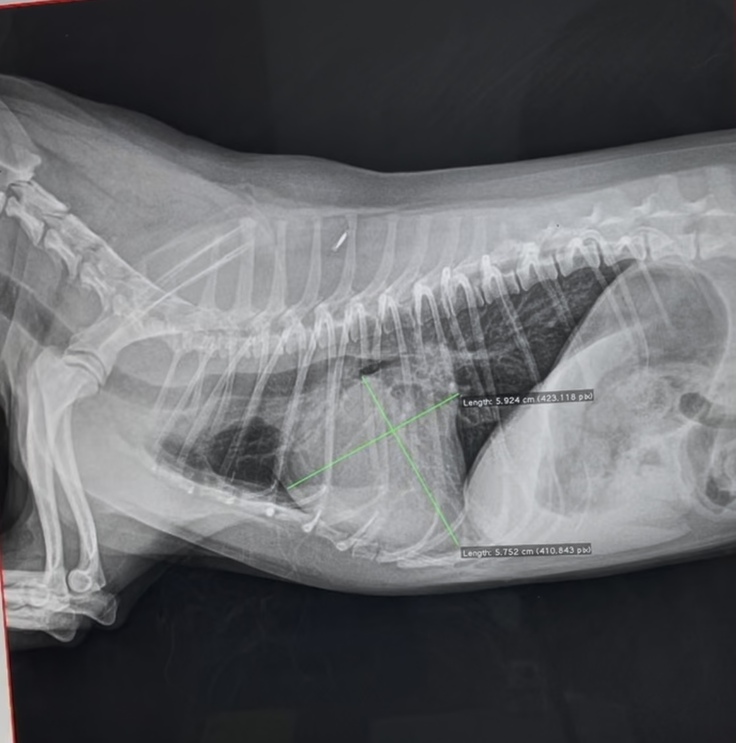

▼肥大した心臓 気管を押し上げてたわみがでています。